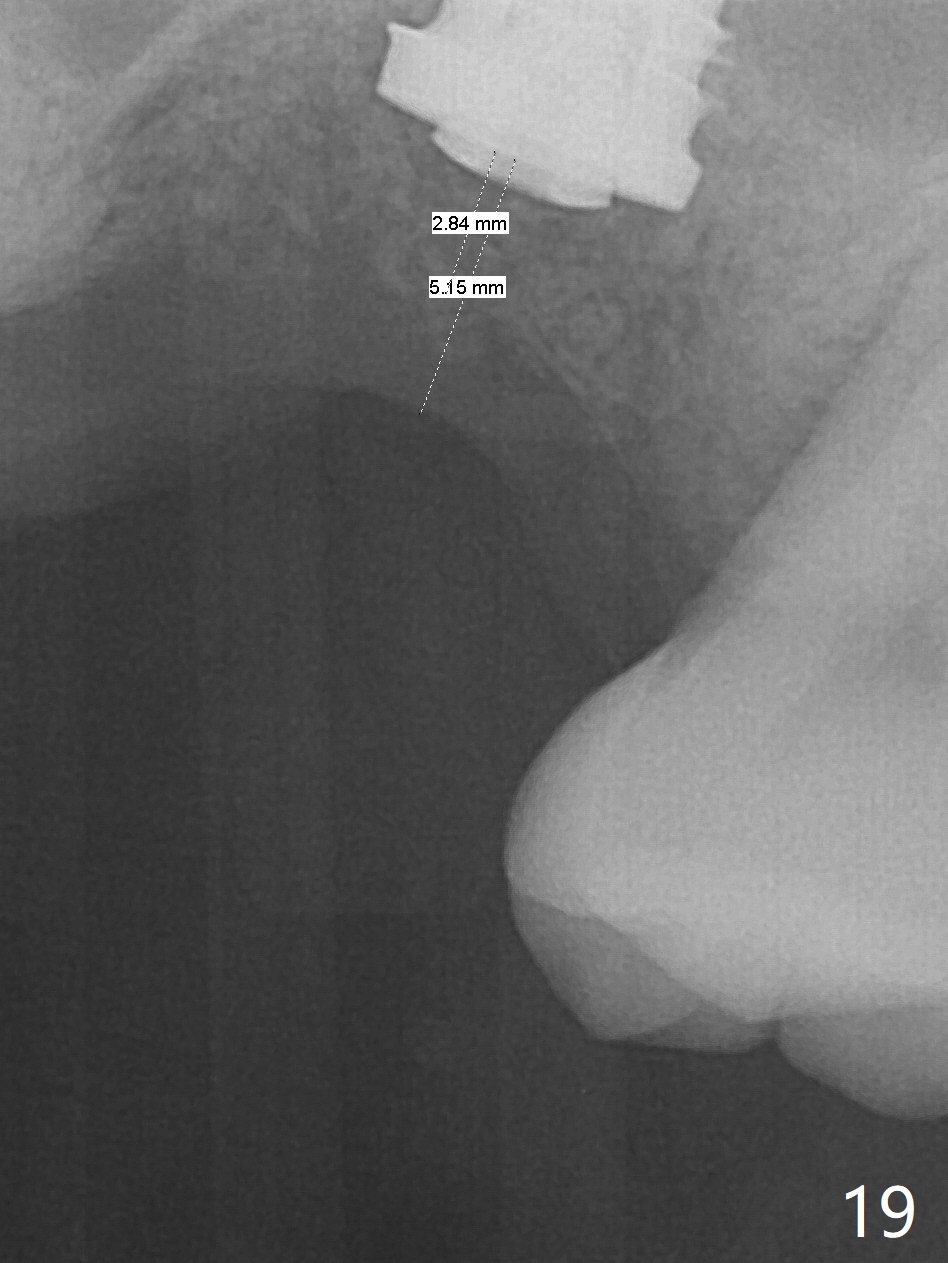

Poor visibility for immediate implant in the molar region is another contributing factor for the dislodgement.  The patient returns for follow up 15 days (Fig.15) and 1 month (Fig.16) postop.  Bone graft seems to be stable around the implant.  The socket heals 4 months postop (Fig.20).  The implant seems to have been osteointegrated (Fig.17,18).  It will be backed up for ~ 3 mm to improve implant/crown ratio (Fig.19, as compared to Fig.14).  If it cannot be done, take impression immediately and make a subgingival provisional before suturing.

In fact, there is no coronal bone for the implant to be backed up.  Therefore, impression is taken after uncover and insertion of a 5.5x5.7(4) mm abutment.